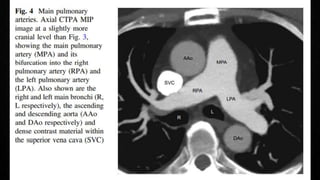

COMPUTERISED TOMOGRAPHIC PULMONARY

ANGIOGRAPHY (CTPA)

• Multidetector CTPA is the method of choice for imaging the pulmonary vasculature in

suspected PE

• PIOPED II Study (Prospective Investigation On Pulmonary Embolism Diagnosis)

observed a sensitivity of 83% and a specificity of 96%

• In patient with a low/intermediate pre-test probability, negative predictive value of a

CTPA to rule out PE was high (96%/89%), but only 60% if the pre-test probability was

high

• The positive predictive value is high (92-96%) if the pre-test probability is intermediate or

high, but much lower (58%) if the clinical likelihood was low

• Remains controversial whether patients with a negative CTPA and a high clinical

probability should be further investigated

• Pre-existing CTEPH should not be missed